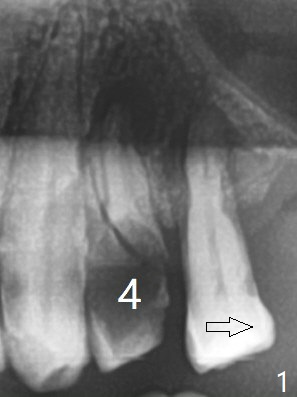

左上4拔除(图三)位点保留(图四:人工骨ß-TCP (beta tricalcium phosphate))图五:GEM Cap)重要,尽管他准备做假牙。